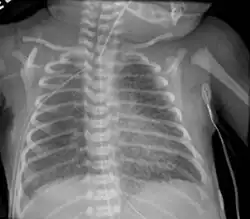

Infant respiratory distress syndrome most commonly occurs in less than six hours after birth in about 1% of all births in the United States.[9] The main risk factor is prematurity with the likelihood of it occurring going up to 71% in infants under 750g.[20] Other risk factors include infant of a diabetic mother (IDM), method of delivery, fetal asphyxia, genetics, prolonged rupture of membranes (PROM), maternal toxemia, chorioamnionitis, and male sex. The widely accepted pathophysiology of respiratory distress syndrome is it caused by insufficient surfactant production and immature lung and vascular development. The lack of surfactant makes the lungs atelectatic causing a ventilation to perfusion mismatch, lowered compliance, and increased air resistance. This causes hypoxia and respiratory acidosis which can lead to pulmonary hypertension. It has a ground glass appearance on an x-ray. Symptoms can include tachypnea, nasal flaring, paradoxical chest movement, grunting, and subcostal retractions.[9]

Pulmonary interstitial emphysema is the condition of air escaping overdistended alveoli into the pulmonary interstitium. It is a rare disease that occurs most often in premature infants, even though it is possible to appear in adults.[26] It often presents as a slow deterioration with the need for increased ventilatory support. Chest x-ray is the standard for diagnosis where it is seen as linear or cystic translucencies extending to the edges of the lungs.[9]